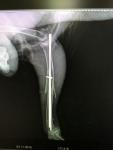

Сложный перелом бедра у грача. Минск.

В результате игры с собакой и моего недосмотра было сломано бедро нездоровой, левой, ноги и есть травма левого крыла.

Все произошло месяц назад. В Минске операций птицам не делают - возили в Москву и делали остеосинтез бедра.

Птица на лапу пока не становится. Был сделан повторный рентген - спицы вынимать еще рано, не срослось. Живем в коробке на тряпочках. И на ручках.

Рентген до операции и сразу после, 2.11 - post-10933-1480620471_thumb.jpg post-10933-1480620493_thumb.jpg

Рентген 23.11 - post-10933-1480620586_thumb.jpg

у вас не бедро -оно ВНУТРИ тела у птиц спрятано, поэтому я так испугалась когда услышала что у вас бедро сломано. У вас- голень сломана. Ниже - цевка.